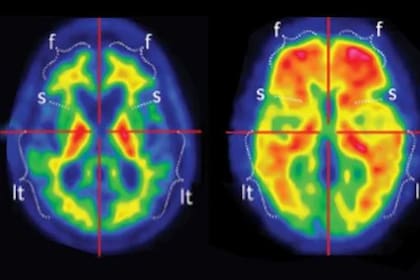

Con el avance de las técnicas de imágenes cerebrales, los investigadores ahora pueden observar cómo estas afecciones se manifiestan en cerebros vivos y los patrones comienzan a mostrar similitudes inesperadas.

Durante años, tanto en el estudio del autismo como en el del Alzheimer, la investigación se concentró en regiones cerebrales aisladas: qué áreas eran más grandes o más pequeñas, más o menos activas. Por ejemplo, a los científicos les llamó la atención que el Alzheimer estuviera asociado con la contracción de una región conocida como la amígdala, vinculada con la emoción, el miedo y el procesamiento social. En el autismo, en cambio, la amígdala suele aparecer agrandada, aunque los resultados han variado según la edad de las personas estudiadas y el diseño de los trabajos.

Cada vez más, sin embargo, el foco se desplazó de las regiones individuales a las conexiones entre ellas: las redes que permiten que el cerebro funcione como un conjunto integrado.

En el autismo, los hallazgos presentados el año pasado en la conferencia anual de la Asociación Neuropsiquiátrica Estadounidense sugieren que la densidad y la fortaleza de las conexiones sinápticas pueden correlacionarse con el nivel de funcionamiento. En algunos casos, una conectividad más sólida se asocia con un mejor desempeño en la vida cotidiana. En el Alzheimer, en cambio, la pérdida de esas mismas conexiones se correlaciona de manera muy estrecha con el deterioro cognitivo, y algunos especialistas consideran que puede tratarse de un indicador anatómico más preciso que la acumulación de placas amiloides o de los ovillos formados por la proteína tau, durante mucho tiempo considerados los rasgos definitorios de la enfermedad.

Cómo evolucionan esas conexiones neuronales con el paso del tiempo —y qué puede revelar ese proceso sobre el envejecimiento en el autismo y sus posibles vínculos con el Alzheimer— se convirtió en una pregunta central, que investigadores como B. Blair Braden comenzaron a explorar.

Su primer trabajo importante sobre el tema, publicado en 2022, detectó cambios en el hipocampo —una región clave para la memoria—, que se contrae con la edad tanto en adultos autistas como en personas no autistas, aunque de manera más marcada y más temprana en quienes tienen autismo.

A Braden le sorprendió comprobar hasta qué punto los estudios por imágenes parecían contar una historia similar a la que emergía de la investigación genética y molecular. “Es increíble ver cómo los resultados empiezan a encajar”, señaló.